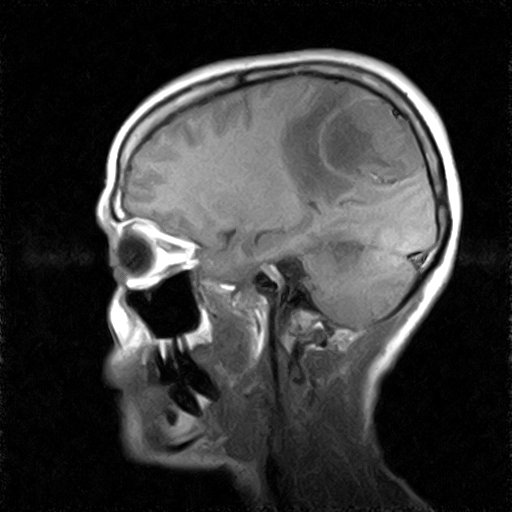

• RESONANCIA PATOLÓGICA DE CRANEO - MENINGIOMA -  SAG T1

• RESONANCIA PATOLÓGICA DE CRANEO - MENINGIOMA -  SAG T2